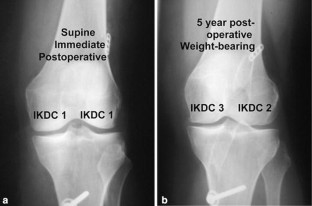

Patellar tendon graft has been the most frequently used material in anterior cruciate ligament (ACL) reconstruction, but the hamstring tendons have been increasingly used as well; however, which graft is to be preferred is not adequately supported by existing clinical studies. In this prospective randomized clinical trial, the study hypothesis was that the hamstring tendons are equally good graft material as the patellar tendon in ACL reconstruction. Ninety-nine patients with laxity due to a torn ACL underwent arthroscopically assisted reconstruction with graft randomization according to their birth year to either patellar tendon with metal interference screw fixation or double looped semitendinosus and gracilis tendons with fixation similar to the Endobutton technique using a titanium metal plate suspension proximally and screw-washer postdistally. Excluding preoperative Lysholm knee score, there were no significant differences between the two groups in the preoperative and operative data. A standard rehabilitation regimen was used for all the patients, including immediate postoperative mobilization without a knee brace, protected weight bearing for 2 weeks, and return to full activity at 6–12 months postoperatively. Forty patients in the patellar tendon group and 39 patients in the hamstring tendon group were available for clinical evaluation at median 5 years after surgery (ranges 3 years 11 months–6 years 7 months). The results revealed no statistically significant differences with respect to clinical and instrumented laxity testing, isokinetic muscle torque measurements, International Knee Documentation Committee ratings, Lysholm (knee score), Tegner (activity level) and Kujala patellofemoral knee scores. There was an enlargement of the drill tunnels, statistically more in the hamstring tendon group, but no increase from 2 to 5 years in either group. Narrowing of the joint spaces (IKDC measurement method) from 2 to 5 years postoperatively was seen in both the groups, however, without difference between the two groups.

Fig. 1